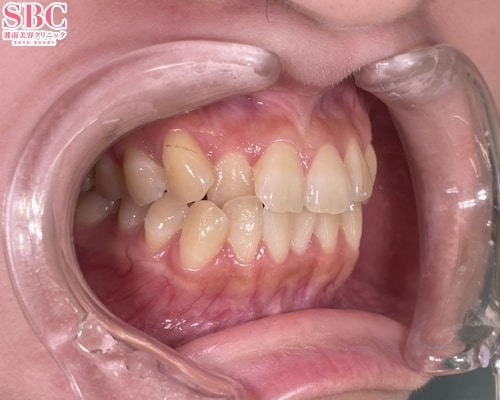

No.342663【美容歯科】【れいな先生】ヤエバにさよなら!全体矯正で歯ならび大変身!MVPドクターならここまでできます☆【マウスピース矯正】

施術前

前歯の見た目が気になる

施術後13ヶ月後

ヤエバが治り、こんなに印象が変わりました

こちらの症例はインビザライン・モデレート両顎の症例になります

やえば含めた前歯の見た目を改善希望しご来院されました

噛み合わせが逆になっているところも含め、全体的に綺麗にさせていただきました

歯ならびが揃うことで、バッカルコリドーも小さくなり、笑顔がより一層綺麗になりましたね